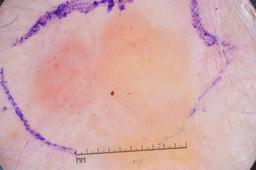

{

"age_approx": 70,

"anatom_site_general": "posterior torso",

"concomitant_biopsy": true,

"dermoscopic_type": "contact non-polarized",

"diagnosis_1": "Benign",

"diagnosis_2": "Benign soft tissue proliferations - Fibro-histiocytic",

"diagnosis_3": "Dermatofibroma",

"diagnosis_confirm_type": "histopathology",

"image_type": "dermoscopic",

"lesion_id": "IL_9502673",

"melanocytic": false,

"sex": "male"

}